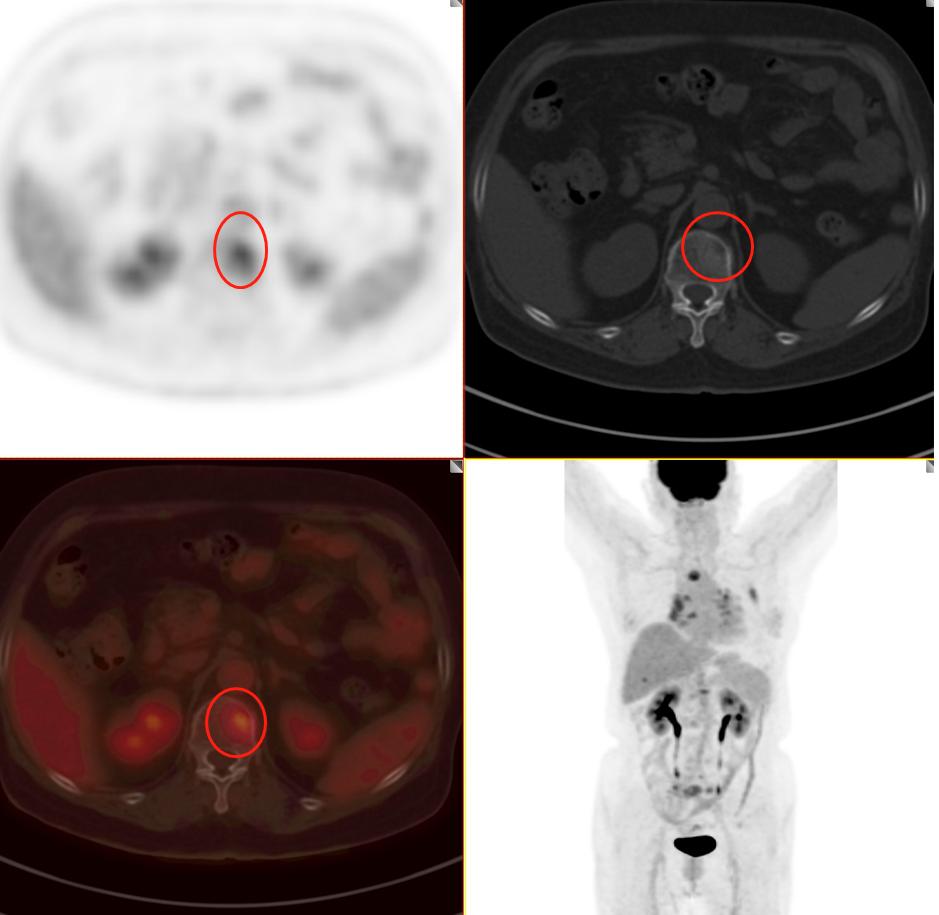

患者1:图3

毫无疑问PET/CT检查18-F-FDG葡萄糖代谢增高,再一次增强了肺癌的诊断信心,影像学可以肯定的诊断为周围型肺癌。其余所示结节未见FDG代谢增高,考虑为慢性炎性结节及钙化灶。

患者1:图4

全身PET/CT检查其他部位未见明显异常放射性浓聚灶,即全身其他部位未发现肿瘤性病变(未见明确转移)。不幸中的万幸,患者没有转移。通过检查可以进行一个肿瘤分期:T1cN0M0 属于ⅠA3期。这一类也算早期肺癌,术后治愈率不错。